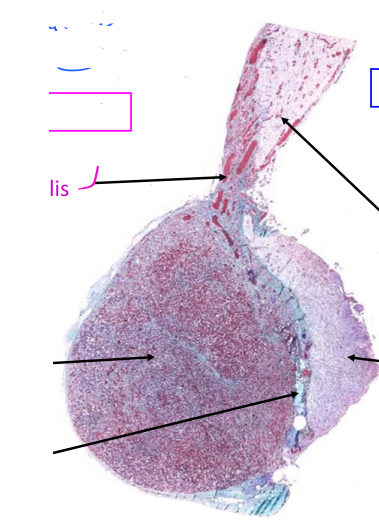

name the cells at the arrows